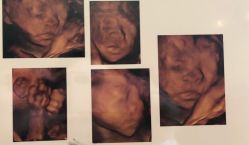

• -郑州万安妇产医院

相册

莉姐 上传于 19-01-08 | 报错